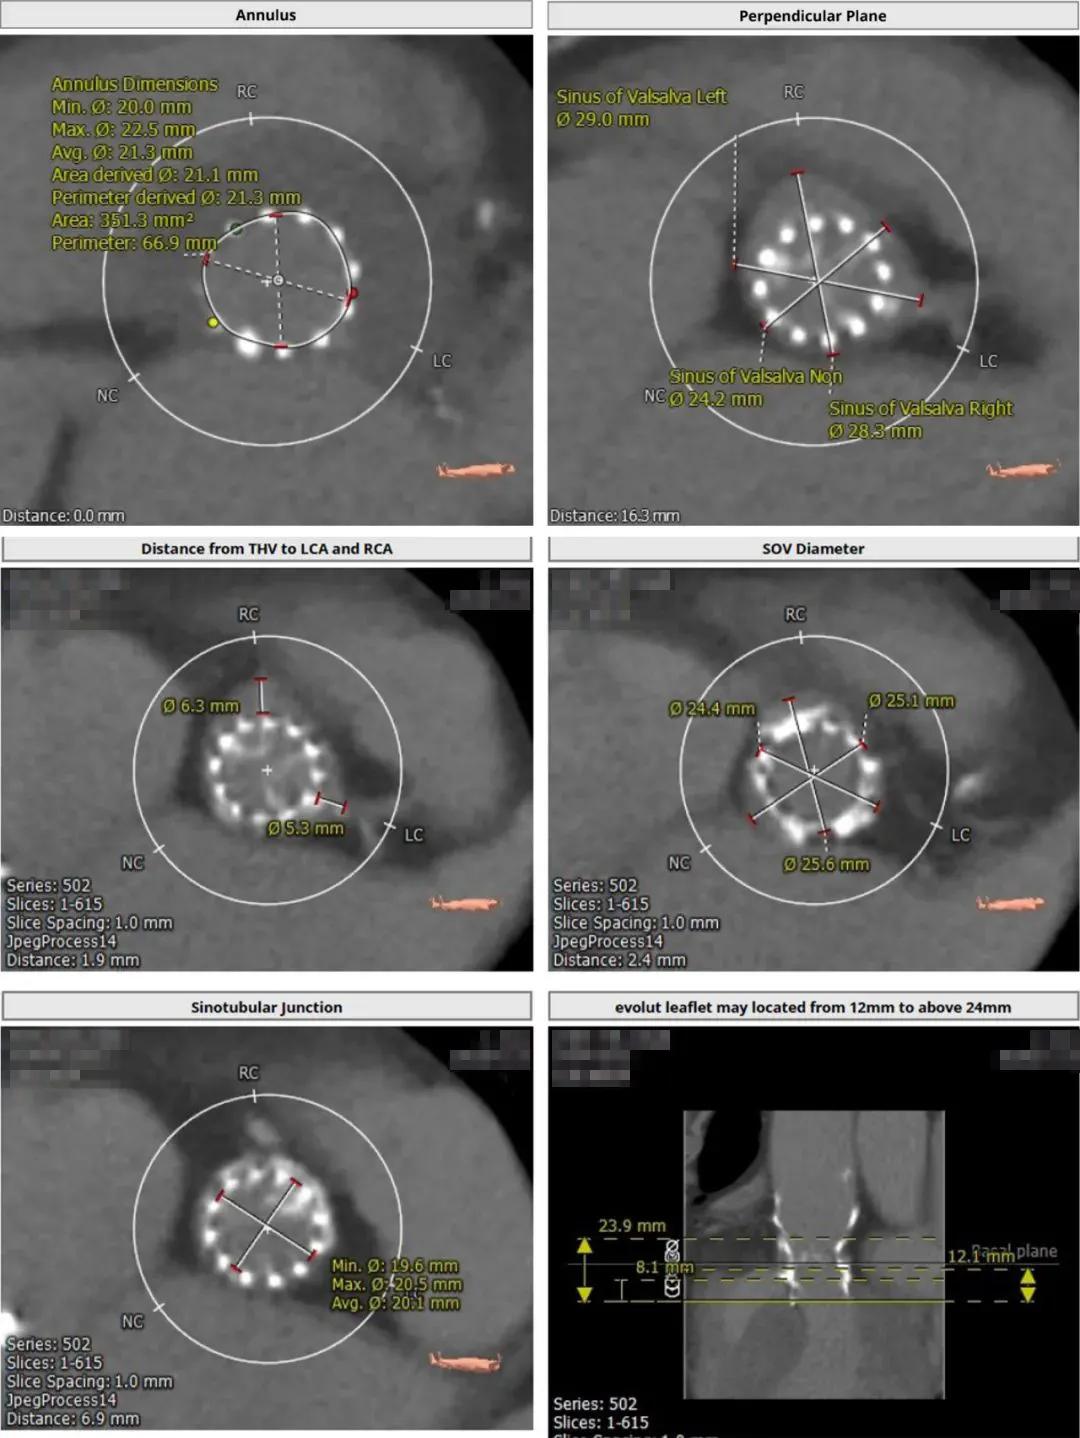

术前CT提示,患者主动脉瓣瓣环平均直径21.3 mm,瓣口面积351.3 mm 2 ;主动脉窦与窦管交界偏小,且冠脉开口偏低,冠脉阻塞风险偏高。该患者既往植入的是一枚美敦力23号Corevalve瓣膜,综合术前评估结果,决定为该患者植入20 mm Sapien 3球扩瓣一枚,并先行球囊扩张处理(BAV),判断瓣膜植入后是否会影响患者的冠脉血流状况。